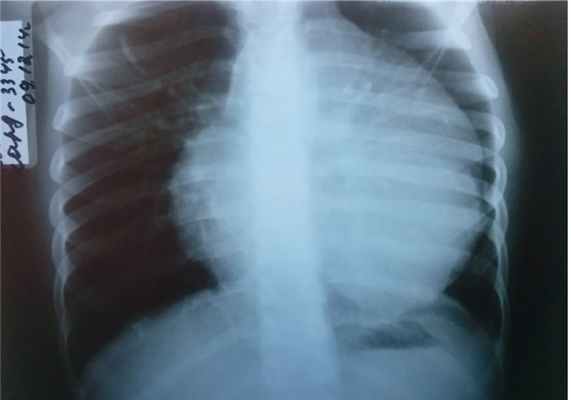

ЭКГ — синусовая аритмия с ЧСС 94 уд/мин (нормокардия). Диффузные изменения миокарда. УЗИ внутренних органов и почек без патологии. Рентгенография грудной клетки показала увеличение размеров сердца ( рис. 1 ).

Рис. 1. Рентгенограмма грудной клетки девочки Т., 9 лет. Иллюстрация В.Г. Молчанова, врача-рентгенолога ГАУЗ АО «Амурская областная детская клиническая больница»